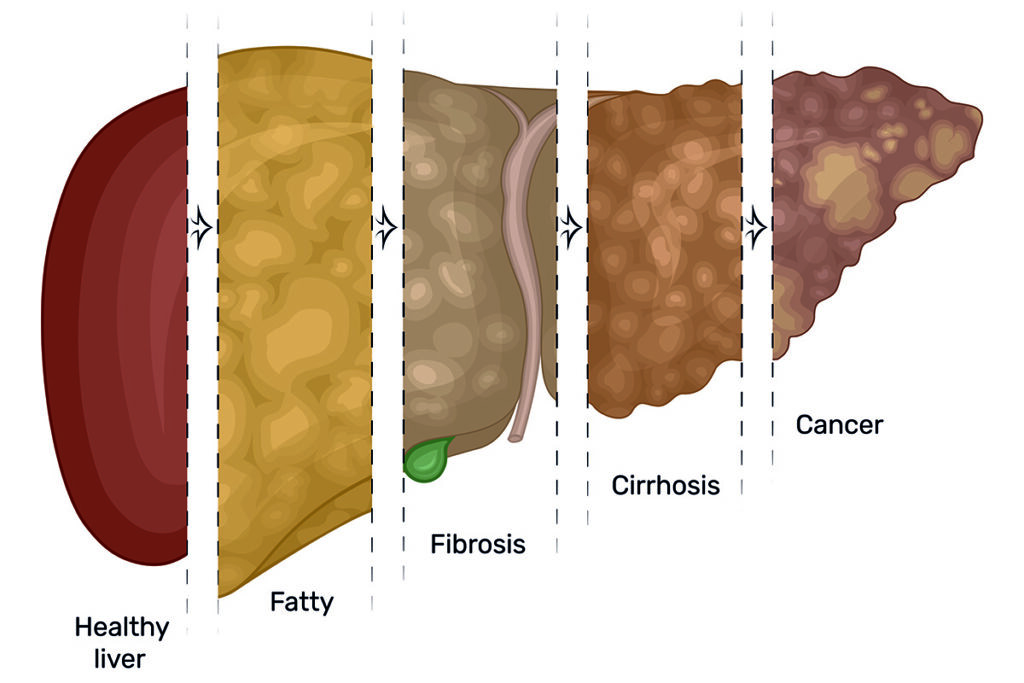

Lemak tambahan dalam hati menyebabkan keradangan hati, yang akhirnya membawa kepada parut (fibrosis) hati.

Seterusnya, ia juga boleh membawa kepada penyakit hati kronik yang lebih serius, seperti sirosis atau kanser hati.

Sesetengah orang yang mengalami sirosis hati yang teruk perlu menjalani pemindahan hati.

Ilustrasi perkembangan penyakit hati daripada hati berlemak kepada kanser.